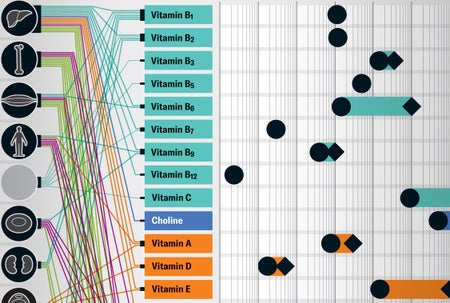

What Vitamins and Minerals Really Do in Your Body

Humans need around 30 vitamins and minerals to keep our bodies functioning